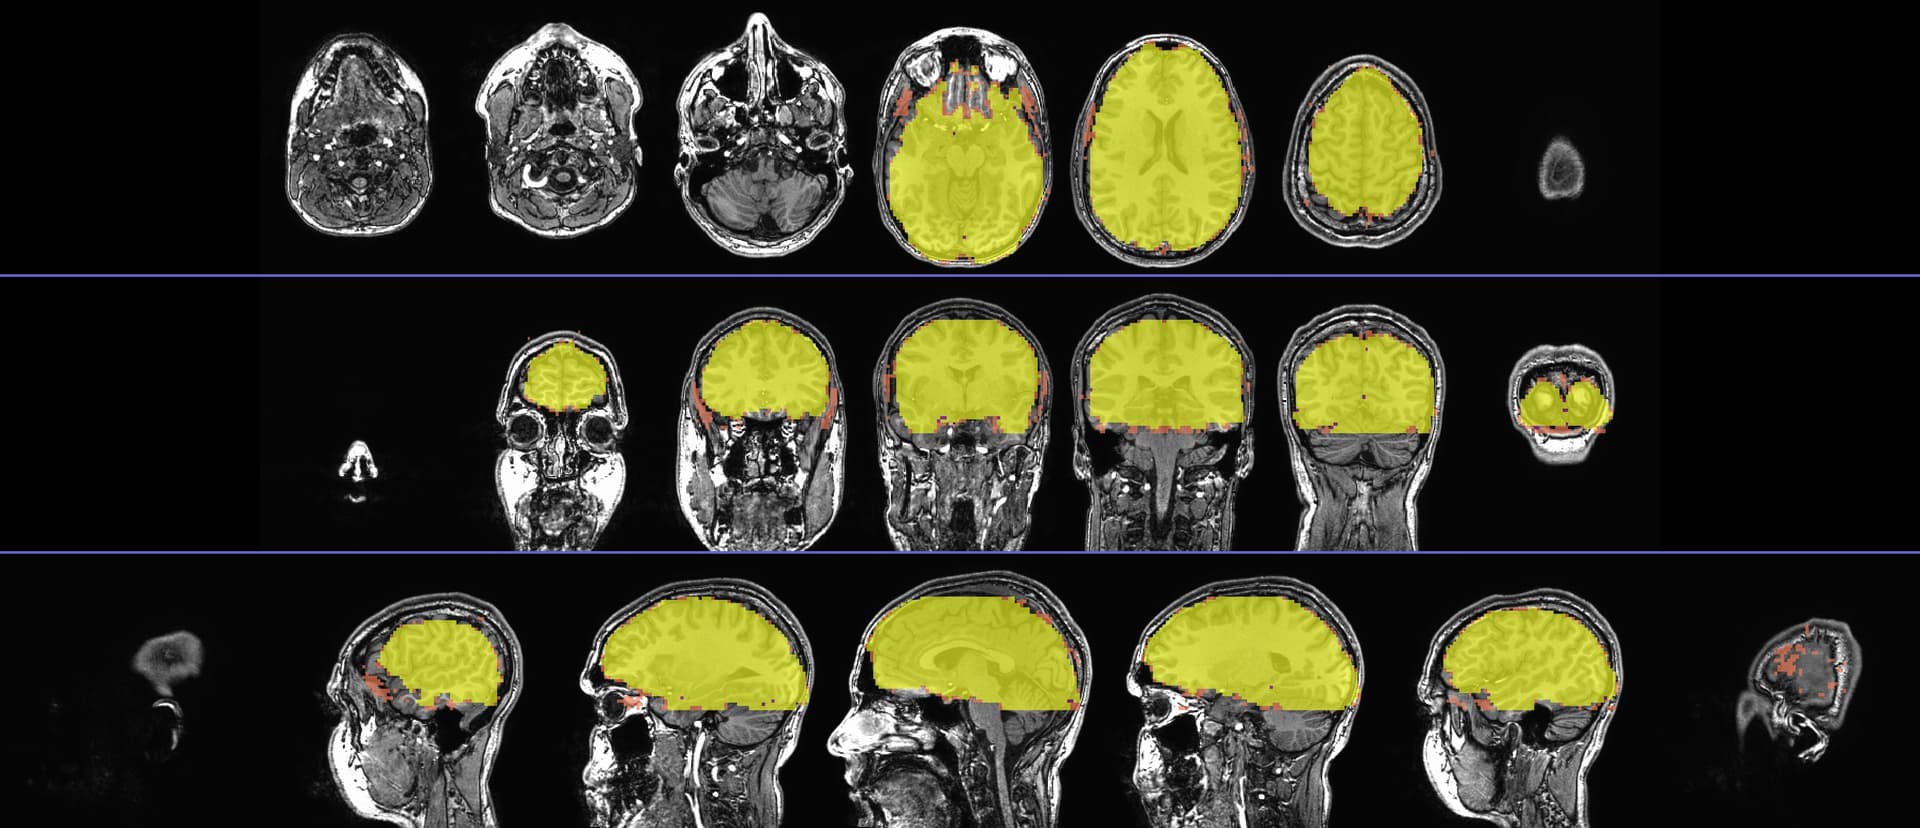

I got the sagittal and axial slice views, as well as the colorbar image with transparent thresholding noted, as follows:

AAA_qc_07_vstat_Full_Fstat.pbar

... which produced: